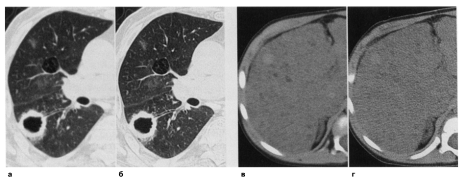

Рисунок 1.4 - Влияние кернеля конволюции на пространственное разрешение и шумы в изображении. В паренхиме легких (высокий естественный контраст) использование кернеля повышенной резкости (б) вместо стандартного кернеля (а) увеличивает резкость изображения. В печени (низкий естественный контраст) мягкий кернель (в) предпочтителен, так как в противном случае (кернель повышенной резкости) (г) увеличивающиеся шумы могут скрадывать структуры с низким контрастом.

Частичный объемный эффект оказывается особенно неблагоприятным при сканировании с плоскостью среза, которая проходит косо или параллельно к границам между тканями (диафрагма, верхушки легких, полюса почек), и при оценке мелких структур (мелкие сосуды, бронхи, надпочечники). Чтобы оценивать структуры, параллельные плоскости среза(например, поджелудочная железа), или для оценки маленьких органов, таких как надпочечники, может потребоваться коллимация 3-5мм. Тонкая коллимация (1-2мм) предпочтительна для легких, где требуется детальный анализ структуры при диагностике интерстициальных поражений. При МСКТ такая коллимация стала стандартной.